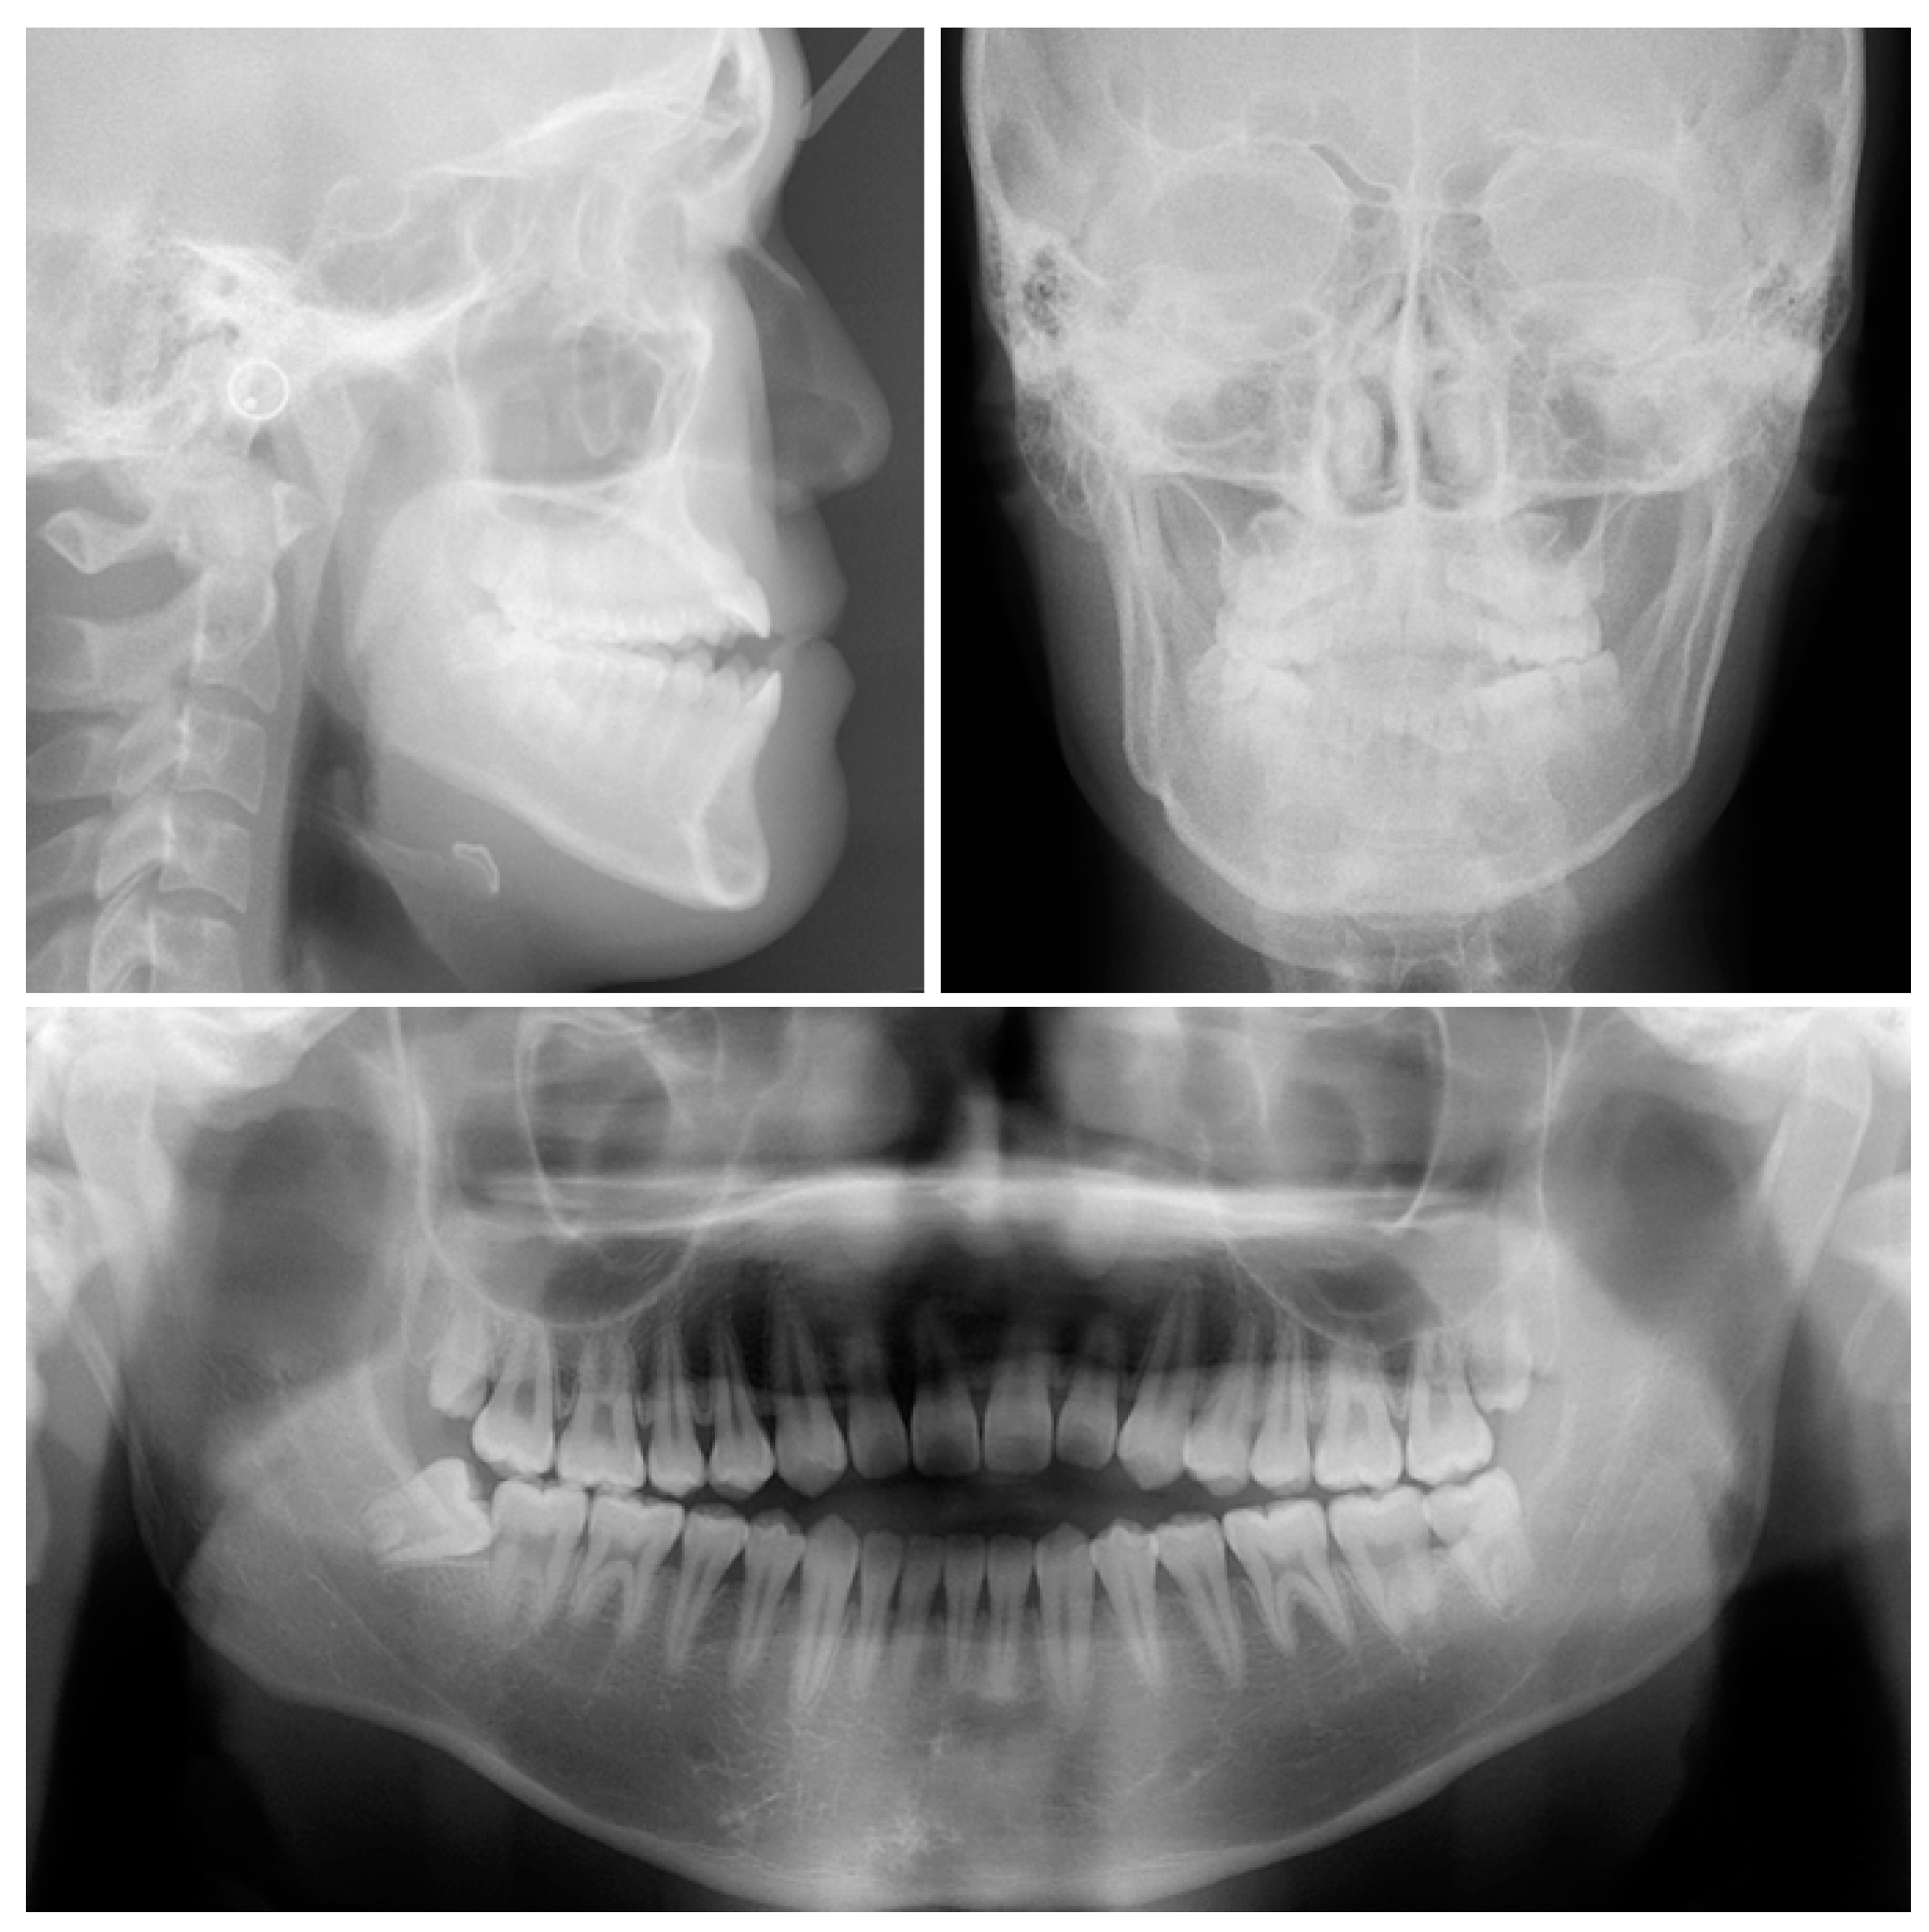

2. Case Report

2.1. Diagnosis and Etiology